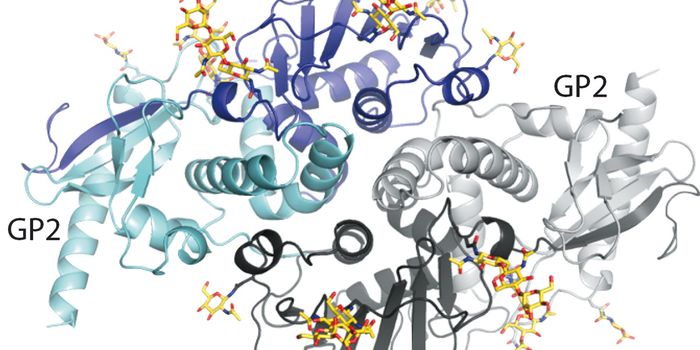

OCT 05, 2021ImmunologyMany of the deadly viruses that affect humans—including Ebola and HIV—have animal origins. These infectious ...

MAY 02, 2016ImmunologyFindings Could Guide Development of Treatments for Lassa Fever For the first time, scientists at The Scripps Research In ...